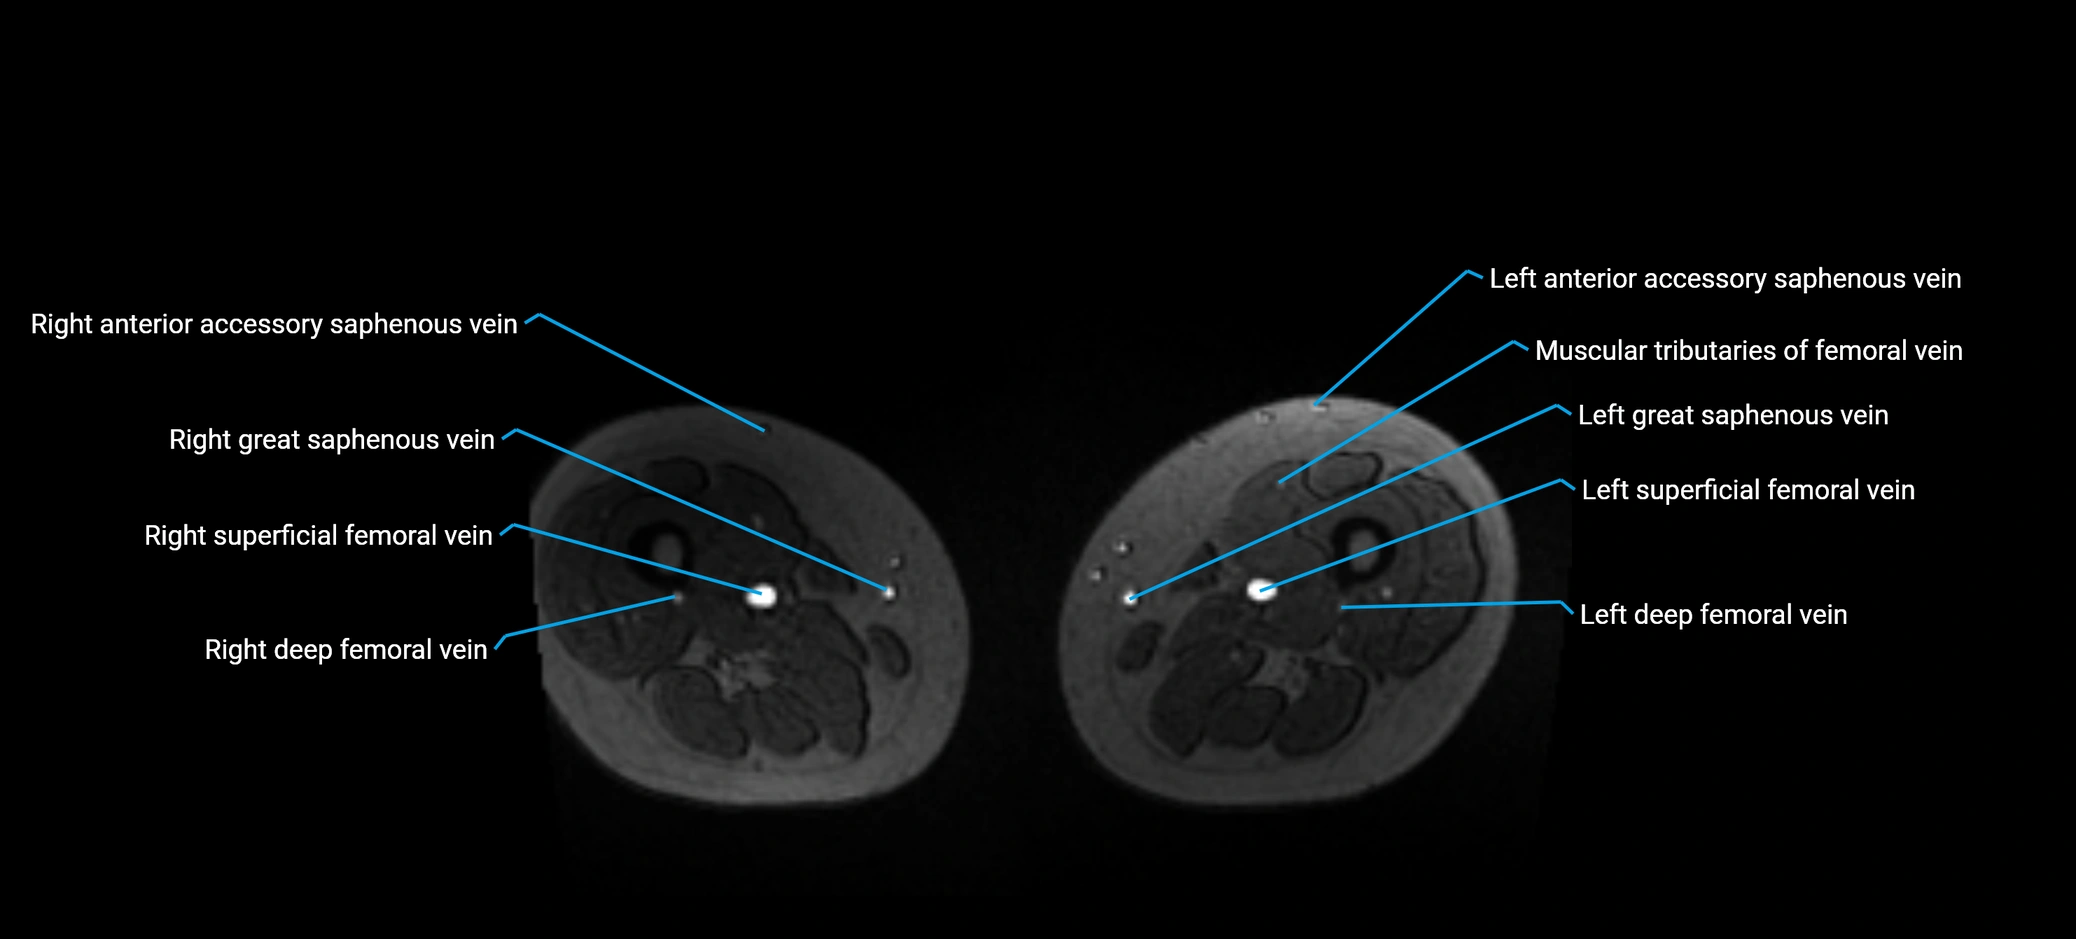

MRI image

image